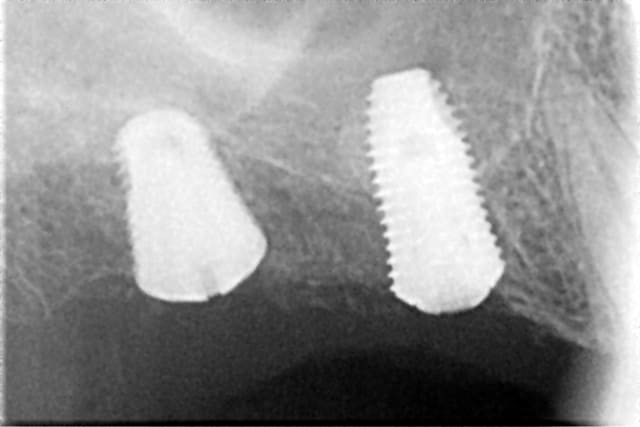

ce sont des implants DENTIUM vendus en france par dentogem

il y a un site internet www.dentogem.com avec tout plein d'infos